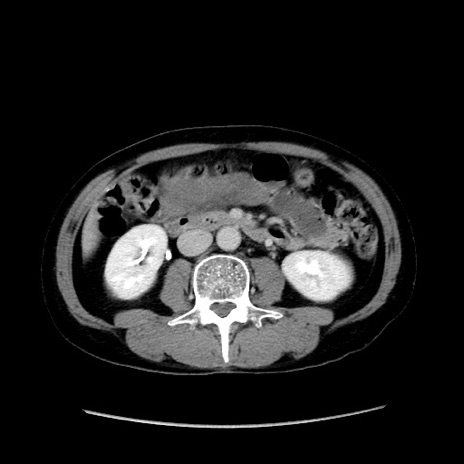

症例37(横断像)

【症例】40歳代 男性

【主訴】腹痛

【現病歴】4時間ほど前に電車に乗車中に臍部上より腹痛出現。徐々に増悪し起立困難となり、救急外来受診。生ものは数日食べていない。今朝お雑煮を食べた。

【身体所見】BT 36.8℃、BP 117/84mmHg、HR 91/min、SpO2 97%、苦悶様、腹部:臍上部広範囲圧痛あり、反跳痛±

【データ】WBC 8100、CRP 0.03